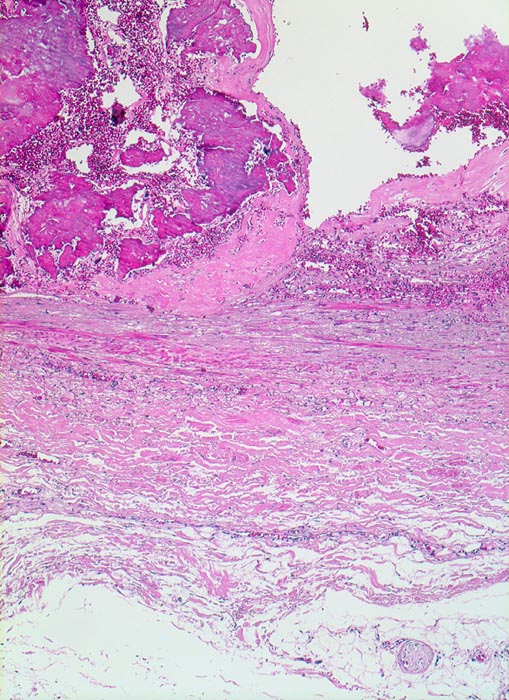

Die Atherosklerose befällt Arterien vom elastischen Typ und die grossen und mittelgrossen Arterien vom muskulären Typ. Die früheste Läsion, der Lipidstreifen, besteht aus einer fokalen Akkumulation von Lymphozyten und glatten Muskelzellen und von Serumlipoprotein in Makrophagen der Intima (> 5267). Zirkulierende Monozyten infiltrieren die Intima, nehmen alteriertes LDL Cholesterin auf und wandeln sich dadurch in Schaumzellen um. Diese Läsion kann sich durch zunehmende Lipidakkumulation und Migration sowie Proliferation von Myofibroblasten zum Präatherom mit wenig extrazellulären Lipidablagerungen und schliesslich zum Atherom (> 9003) mit zentral konfluierten extrazellulären Lipidmassen (> 9004) und nekrotischem Detritus weiterentwickeln. Die eingewanderten Mediamyozyten produzieren extrazelluläre Matrix, welche über dem Atheromkern aus extrazellulärem Lipid, Schaumzellen, Kalziumsalzen und Zellschutt eine fibröse Deckplatte bildet. Die atheromatöse Plaque kann narbig umgebaut werden, dystroph verkalken und konsolidieren oder zu einer komplizierten Plaque fortschreiten. Komplizierte Läsionen sind charakterisiert durch Ulzeration, Thrombose oder Plaqueeinblutungen. Bei einer Verletzung des Endothels oder einer Ruptur der fibrösen Deckplatte kommt der thrombogene Inhalt des Lipidkerns in Kontakt mit dem zirkulierenden Blut und es bildet sich eine Gefässthrombose. Wiederholte Rupturen mit nachfolgender Organisation der Thrombose vergrössern die Plaque und führen zu einer zunehmenden Gefässeinengung. Bei langsam gewachsenen schweren Stenosen bildet sich oftmals ein guter Kollateralkreislauf aus, welcher bei plötzlichem Gefässverschluss einen Infarkt im Versorgungsgebiet der verschlossenen Arterie verhindern kann. Grosse inter- und intraindividuelle Unterschiede bezüglich der relativen Anteile von weichen atheromatösen und derben fibrotischen bzw. verkalkten (> 4557) Bestandteilen der Plaques bestimmen wesentlich die Stabilität bzw. Vulnerabilität der Läsionen. Der Lipidanteil liegt bei rupturierten Plaques generell höher als bei Plaques mit intakter fibröser Deckplatte.

• Intimafibrose mit fokalen grobscholligen(dystrophen) Verkalkungen und Einblutungen in der unteren Hälfte des Arterienquerschnitts.

• Fibröse bindegewebige Deckplatte über dem Atheromkern

• Atherome in der Intima mit zentraler Nekrose, Cholesterinkristallen, Entzündungszellen und gelben Hämosiderinablagerungen oder Einblutungen.

• Partielle Zerstörung der Lamina elastica interna.

• Atrophie der glatten Muskulatur der Media.